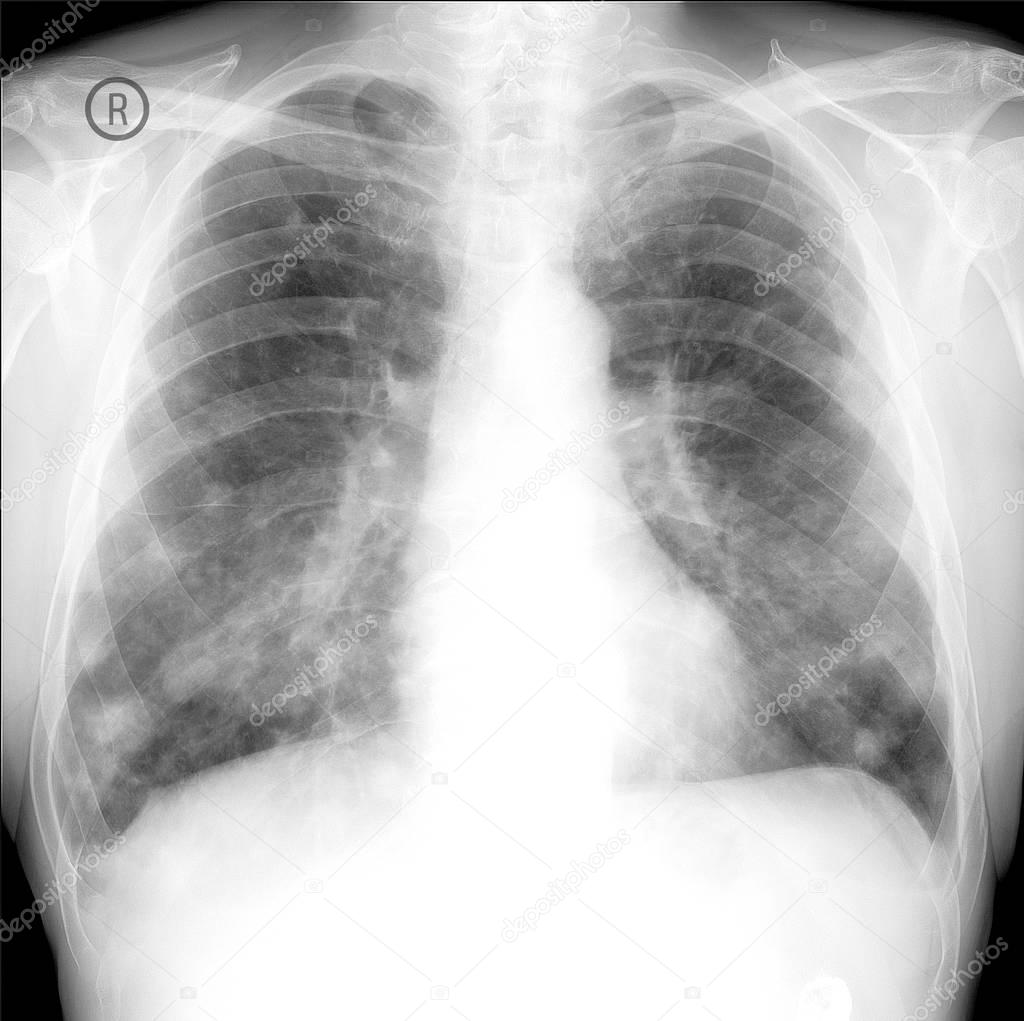

Xray of Patient with Lung Cancer Stock Photo Image of radiology Is Lung Cancer Found On Xray If you have symptoms that worry you, a healthcare. Signs and symptoms of lung cancer. The short answer is no. A ct scan usually isn't enough to tell whether a lung lesion is a benign tumor or a cancerous lump. Lung cancer typically doesn't cause symptoms early on. A biopsy is the only way to confirm a lung. Symptoms of. Is Lung Cancer Found On Xray.

Secondary Lung Cancers, Xray Photograph by Du Cane Medical Imaging Ltd Is Lung Cancer Found On Xray Symptoms of lung cancer usually happen when the disease is advanced. A ct scan usually isn't enough to tell whether a lung lesion is a benign tumor or a cancerous lump. Signs and symptoms of lung cancer. Lung cancer typically doesn't cause symptoms early on. A biopsy is the only way to confirm a lung. A 2017 study found that. Is Lung Cancer Found On Xray.

Advanced metastatic lung cancer Image Is Lung Cancer Found On Xray Lung cancer typically doesn't cause symptoms early on. If you have symptoms that worry you, a healthcare. Symptoms of lung cancer usually happen when the disease is advanced. A 2017 study found that 45% to 81% of missed lung cancers occurred. A biopsy is the only way to confirm a lung. Most lung nodules aren’t cancerous. Lung cancer diagnosis often. Is Lung Cancer Found On Xray.